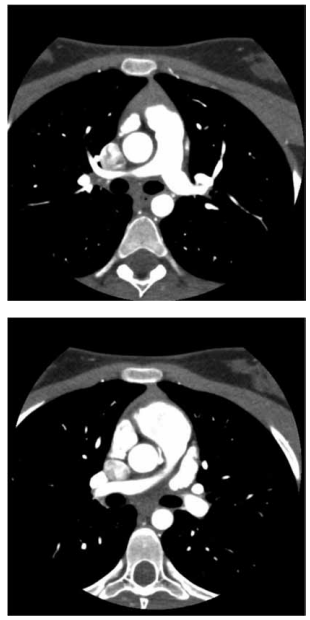

Analise a imagem a seguir.

(Arquivo pessoal; imagens usadas com autorização)

O risco cardiovascular desse paciente com a angiotomografia apresentada é de

tromboembolismo pulmonar agudo.

morte súbita.